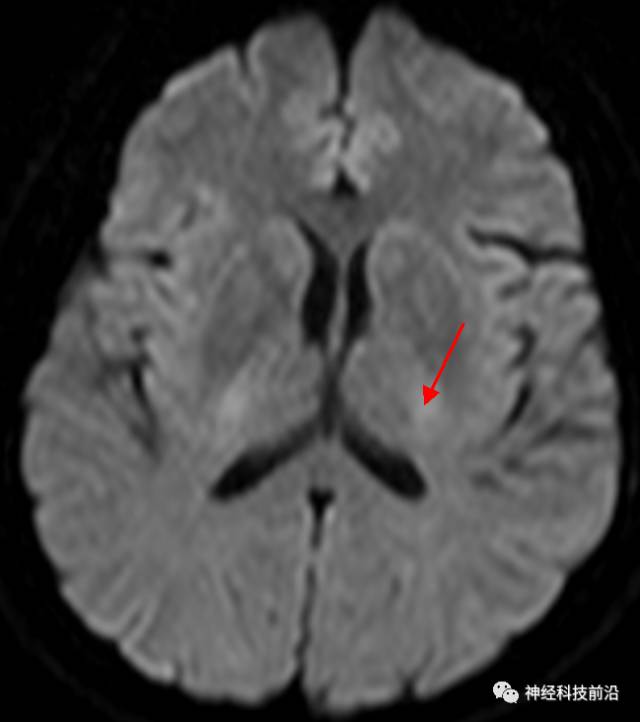

DWI序列脑干、内囊后肢高信号纤维束解析

DWI脑干和内囊后肢经常显示为高信号,它是什么纤维束呢?皮质脊髓束?

脑干内高信号为一近环形纤维束,其作用尚待研究。

终上所述:脑干高信号为一近环形纤维束,内囊后肢高信号为皮质脑桥束,皮质脊髓束在中脑位置略靠后。高信号位于中脑前缘,是皮质脑桥束的位置所在,另外有部分桥连纤维。